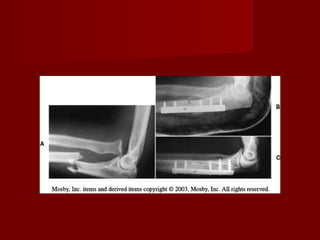

FRACTURAS DEL

OLECRANON.

   En fracturas       no desplazadas,     debe

realizarse reducción cerrada.

   La reducción debe ser exacta.

   Las complicaciones más frecuentes son:

seudoartrosis y la pérdida de la movilidad,

sobre todo en extensión.

   Su mecanismo puede ser: directo e indirecto.

  Los métodos habituales del tratamiento

quirúrgico pueden ser:

1. Reducción abierta y fijación interna con cerclaje

funcional en ocho de guarismo.

2. Fijación medular.

3. Combinación de fijación medular con aguja o

tornillo y cerclaje a tensión.

4. Placa moldeada a mano y tornillos.

5. Extirpación del fragmento proximal.

 Ventajas de reducción abierta y fijación

interna:

1. Permite la reducción anatómica.

2. Permite movilización precoz.

3. Conserva la estabilidad del codo.

4. Se mantiene poder extensor del triceps